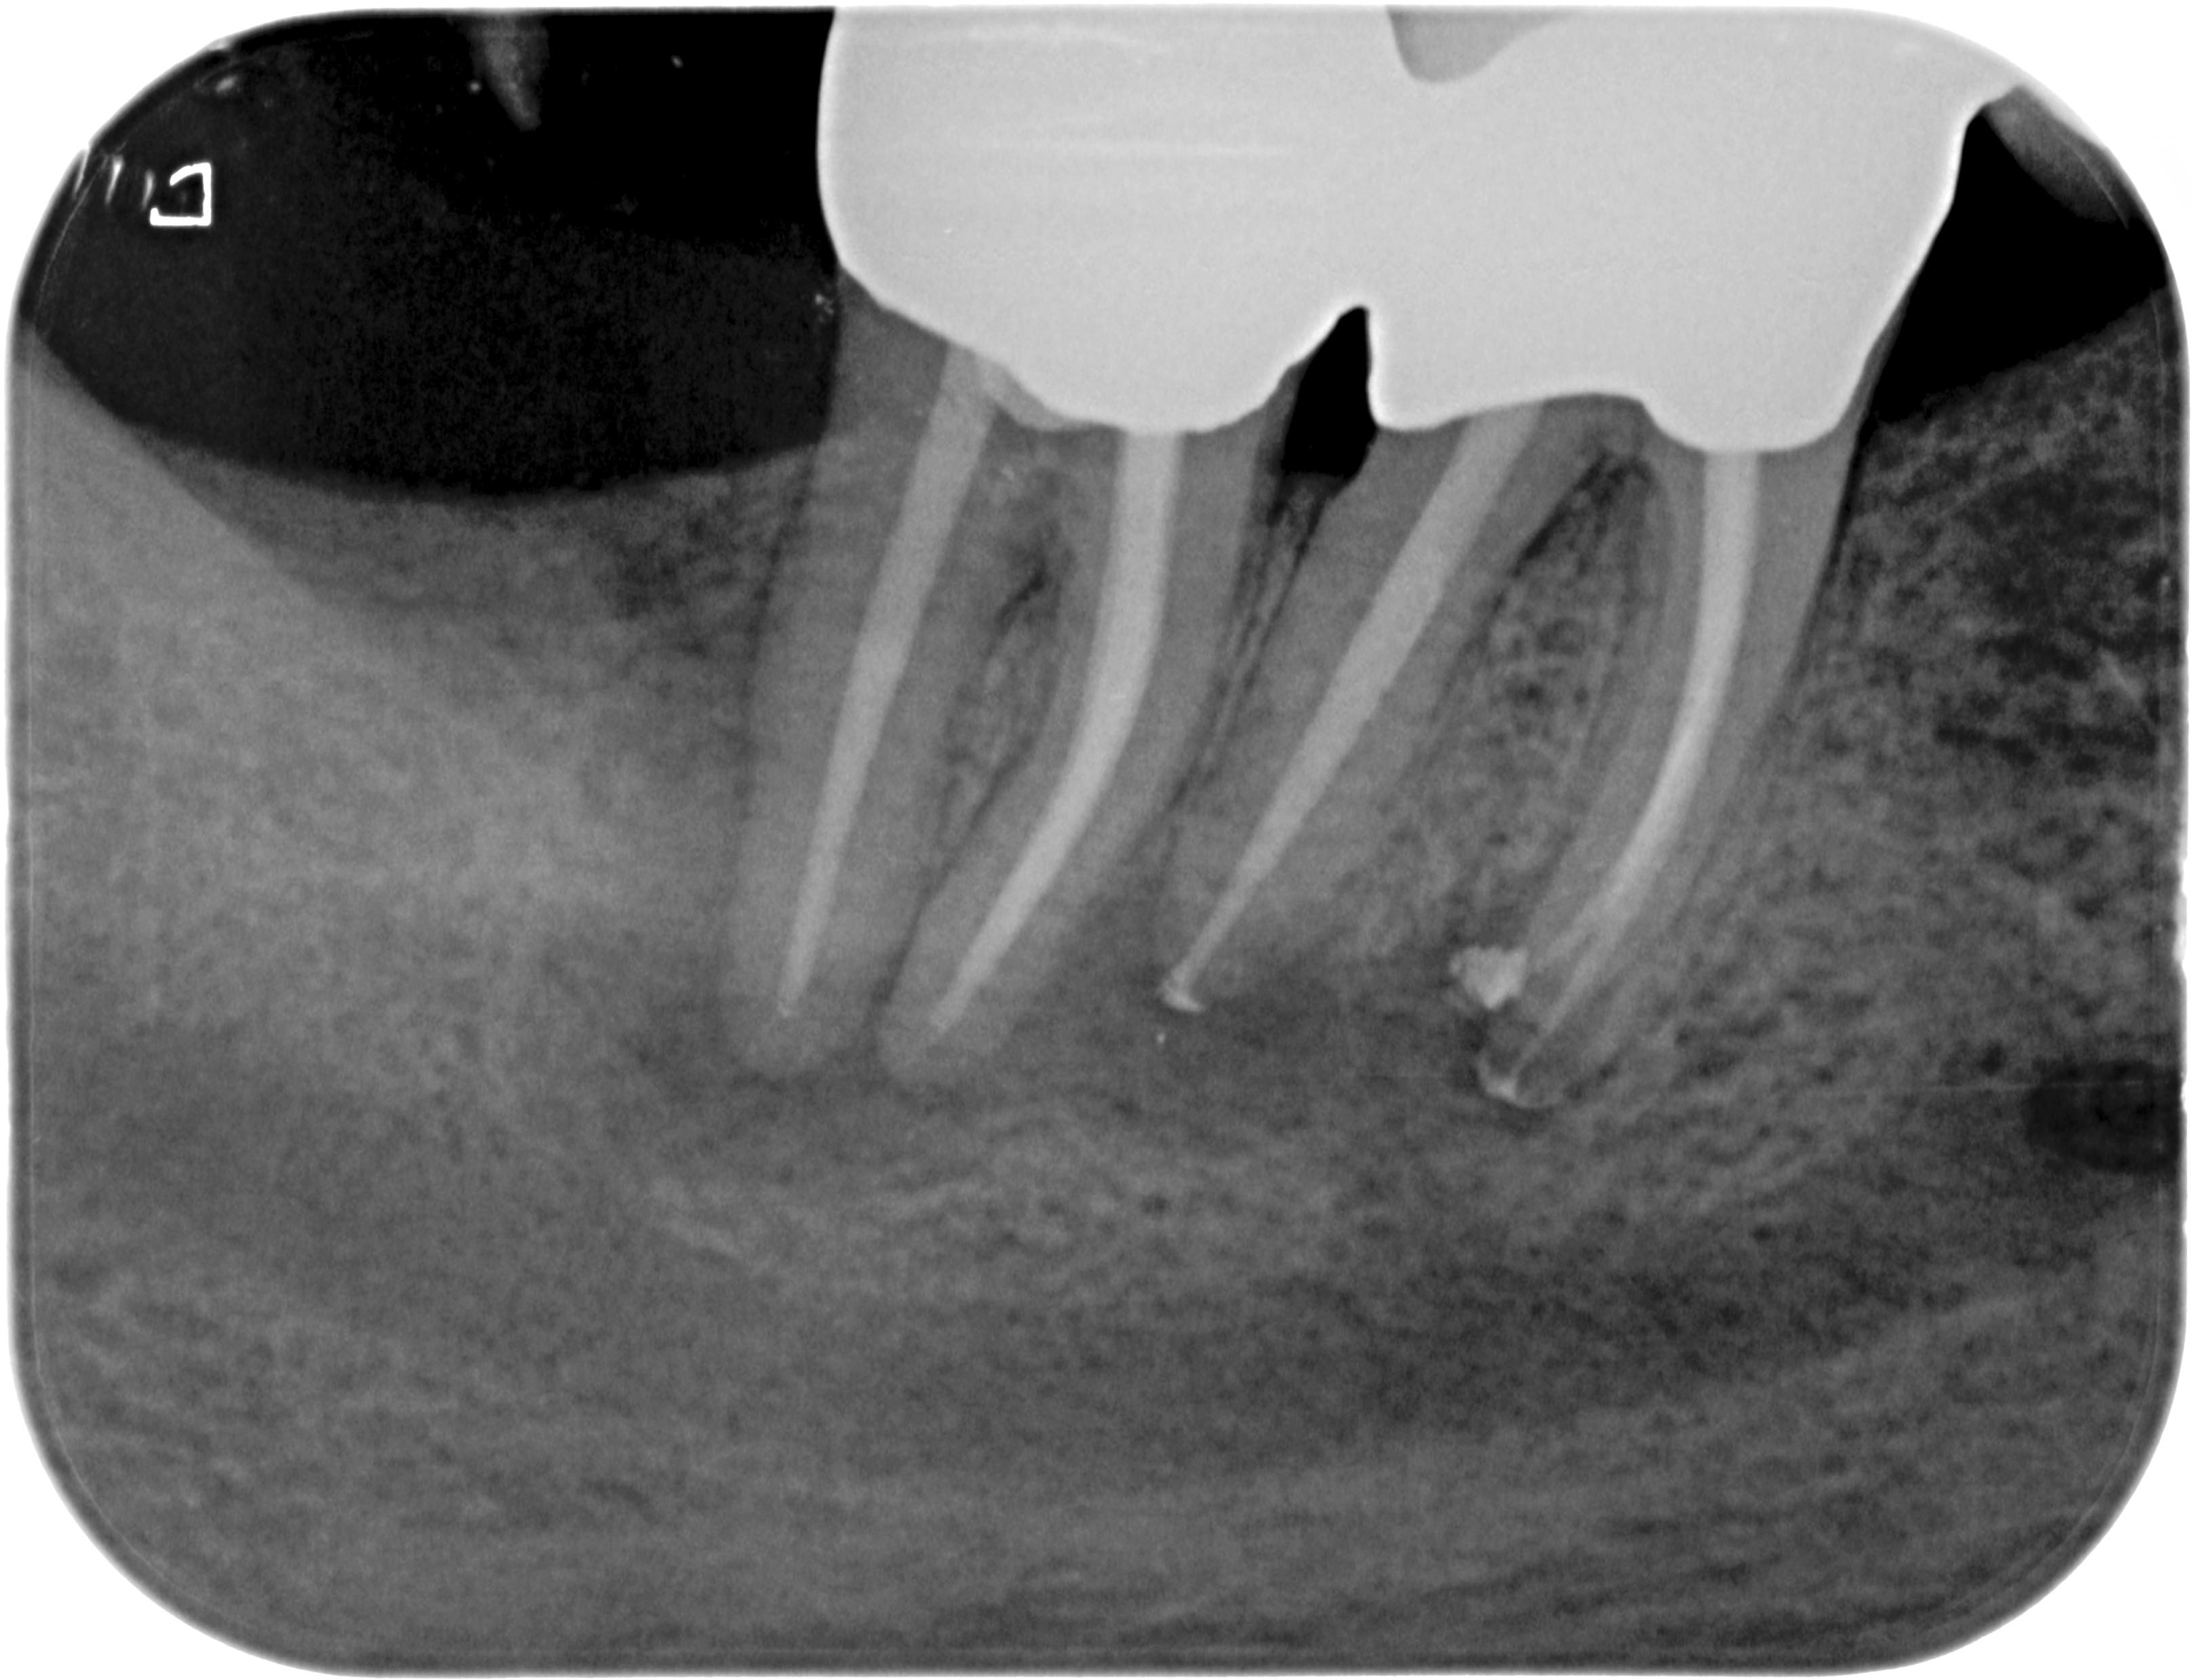

PR4746 (1 von 1) Veröffentlicht 8. April 2013 am 3233 × 2478 in Was zeigt das DVT (2) – Die Auflösung Rö 47 46 post WF